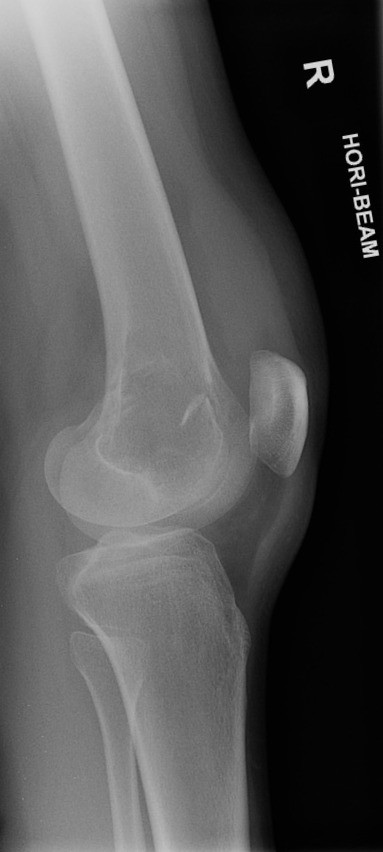

U tế bào khổng lồ

» Thông tin: Nữ giới – 31 tuổi.

» Lâm sàng: Đau khớp gối.